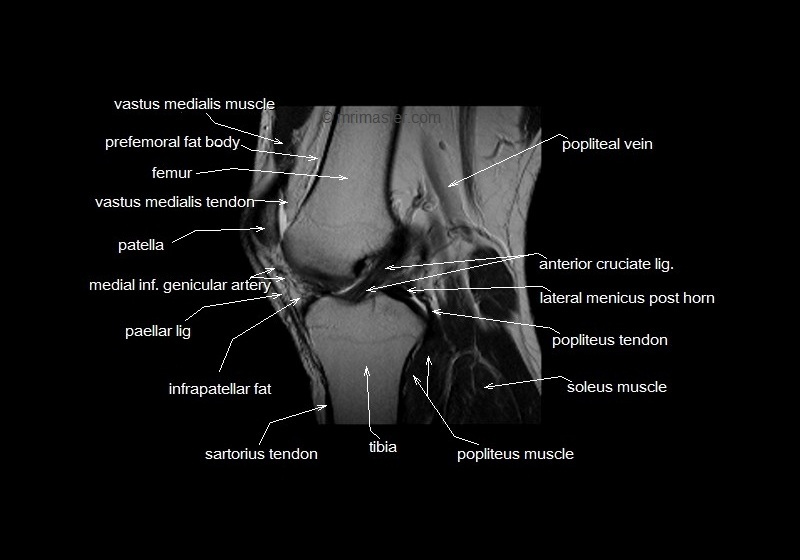

What is this image? Label

T1 weighted MRI of knee, sagittal view